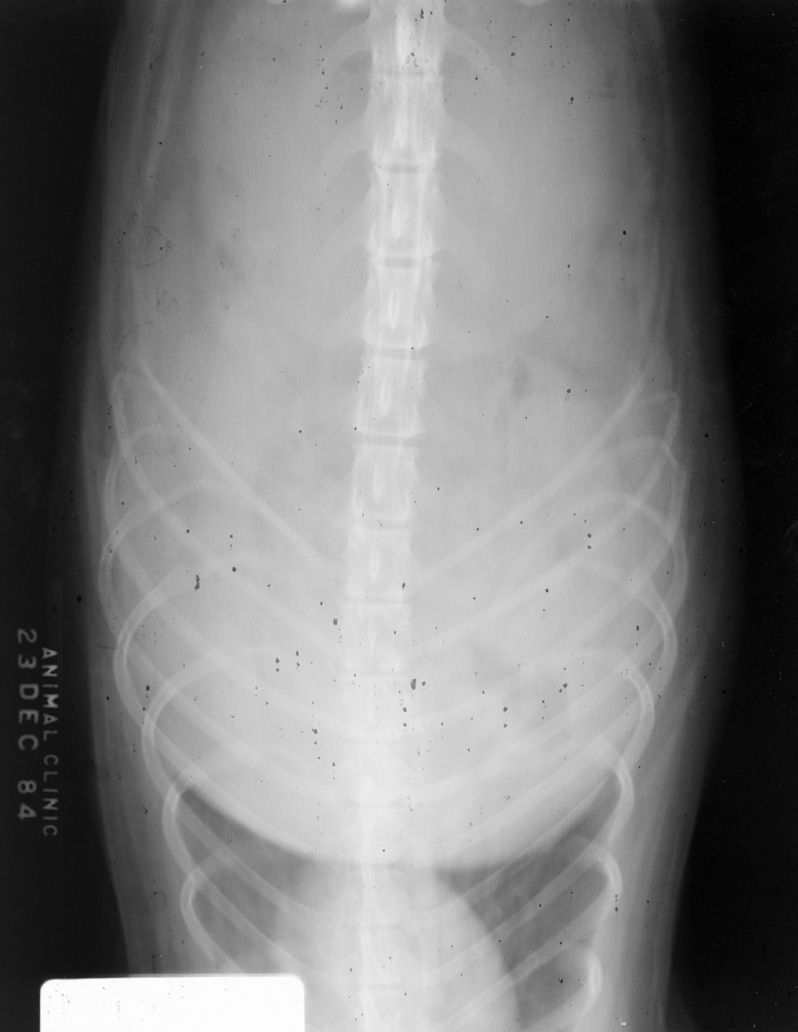

Algae and debris from collars on film. Look at films with both reflected and transmitted light to appreciate this.